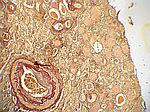

Arterio-Arteriosklerose, EvG